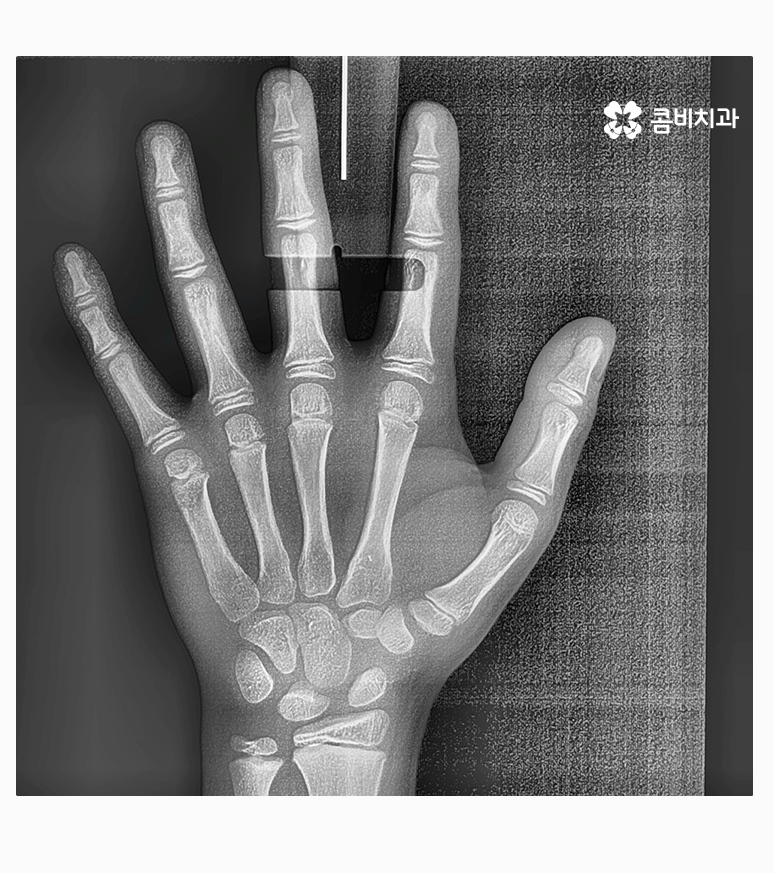

아직 성장이 진행되고 있는 나이에 치아교정을 하면 치아와 골격, 얼굴형 뿐 아니라

성장에 대한 예측을 함께 해야 하기 때문에 보다 세심한 진료와

경과를 자주 살펴보면서 치료가 안전하게 진행되는 것이 중요할 수 있는데요.

부정교합을 치료하는 방법은 나이대와 어떤 상태인지 진단에

따라서 달라질 수 있는데 위 케이스처럼 일반적인 치아교정으로

진행이 되는 경우도 있고 구외 교정 장치를 활용하는 경우 등 진단에 따라 다양할 수 있어요.